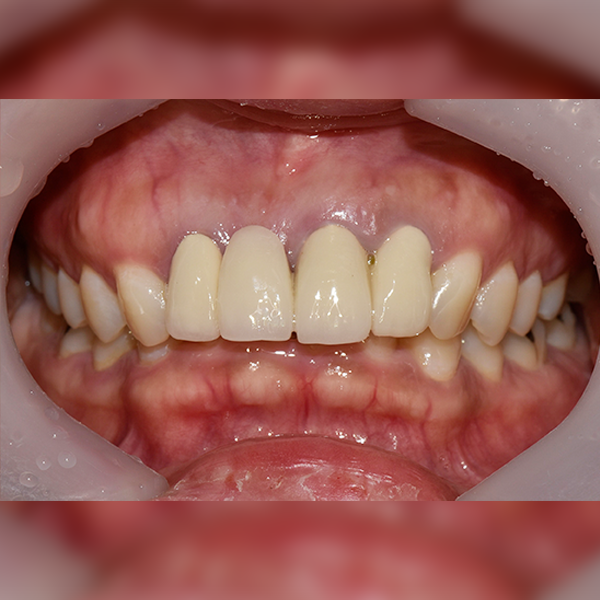

3. 案例.111 30多歲 趙*善 2018-11-30 / 2019-12-10

上顎 / 前牙部位 / 3顆以下 / 補骨

案例.111 30多歲 趙*善 2018-11-30 / 2019-12-10

After After

Before Before